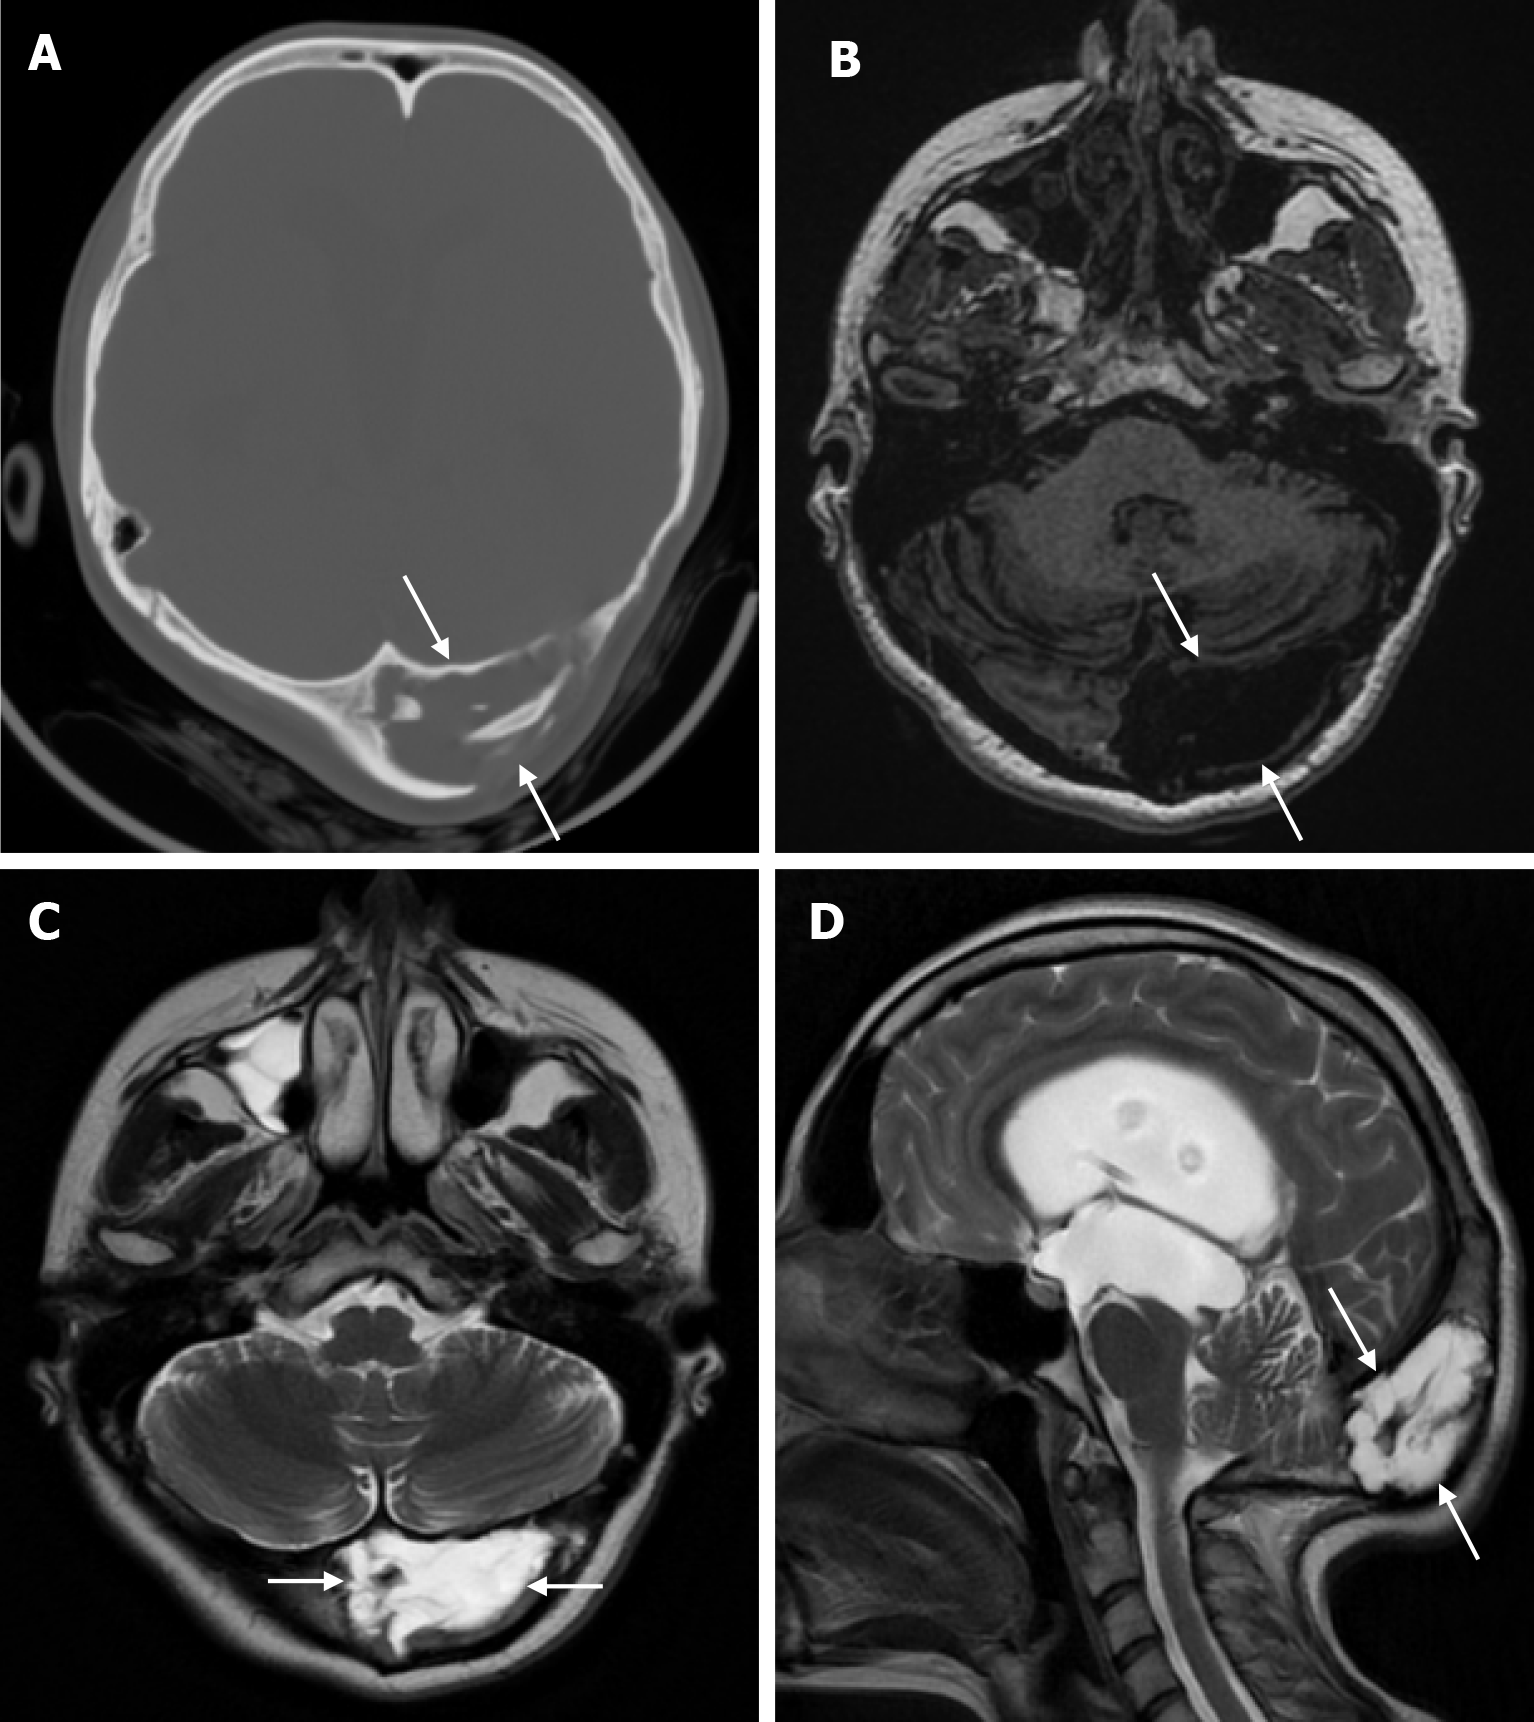

Arachnoid granulations (Pacchionian granulations) are cerebrospinal fluid-filled projections that extend from the subarachnoid space through openings in the dura into the venous sinuses and can be seen macroscopically. Their incidence varies from 0.3% to 55%. Arachnoid granulations are usually seen in millimeter dimensions, but may grow to fill the dural sinuses or arch the inner table[11]. In addition, intraosseous arachnoid granulations can sometimes extend to the inner table of the bone, causing scalloping, remodeling or bone erosion of the inner table[12]. The prevalence of arachnoid granulations increases with age, but there is no difference in gender distribution. Arachnoid granulations with a slight left hemispheric predominance are found in the dural venous sinuses, most frequently in the transverse sinuses and especially in the middle or lateral parts. The second most common location is the superior sagittal sinus, but they can be found anywhere in the dural venous sinuses. Arachnoid granulations are usually detected incidentally. If they fill and expand the dural sinuses, causing partial sinus obstruction, they may cause symptoms of increased intracranial pressure due to venous hypertension. They are usually associated with headaches. Arachnoid granulations may be seen as radiolucent areas on plain radiography of the skull or may cause compression on the inner table of the skull. On CT imaging, arachnoid granulations can be seen as sharply demarcated, hypodense structures in close relation to the dural venous sinus. On MRI, they usually show hyperintense signal on T2-weighted images and hypointense or isointense signal on T1-weighted images compared to brain parenchyma (Figure 1). On CT angiography, MR angiography or catheter angiography imaging, arachnoid granulations appear as oval or round filling defects in the dural venous sinuses during the venous phase[11]. Recent advances in radiology have made it possible to identify brain herniations into the arachnoid granulation by improving image quality with higher resolution and thinner slice three-dimensional T1-weighted and T2-weighted MRI sequences (Figure 2). Brain herniation into the arachnoid granulation is rare in the literature, and the incidence of brain herniation into the calvarial or dural sinuses has been reported to be 0.32%[13]. Arachnoid granulations may be confused with pathological processes in the dural venous sinuses[11]. In the differential diagnosis of arachnoid granulations, venous sinus thrombosis, dural-based tumors, or structures such as septa and fat that may cause filling defects in the dural venous sinuses should be considered[12]. Dural sinus thrombosis usually fills an entire sinus segment or several sinuses and may extend to the cortical veins, whereas arachnoid granulations appear as focal and well-defined defects. Fresh thrombus in the dural sinuses are hyperdense on CT and hyperintense on T1-weighted MRI. Differential tumor diagnosis can be made based on its shape, lack of contrast enhancement and diffusion restriction[11].

Lacunar skull, also known as Lückenschädel, is a fetal ossification disorder described in the early 19th century and rarely seen as an isolated defect. In this ossification defect, shallow or deep cavities form in the flat bones of the inner table of the skull due to mesenchymal dysplasia during intramembranous ossification. Lesions can be seen in any part of the skull but are more prominent in the frontal, parietal, and upper occipital bones. Lacunar skull development begins in utero but disappears by six months. Although it is not usually associated with any medical problem, it is painful when applied to the skin with local pressure, and these patients are at greater risk of brain damage from local trauma. Lacunar skull is often associated with neural tube defects, including spina bifida, meningocele, myelocele or encephalocele. Other congenital developmental anomalies such as rib and limb deformities, microcephaly, cleft palate and craniosynostosis may be present. A direct radiograph reveals that the craniolacuna has a distinctive "honeycomb" or "soap bubble" appearance. Large, rounded areas of reduced bone density are bordered by a pattern of thick bone that resembles a spiderweb. However, three-dimensional CT clearly shows numerous oval and round lacunae[17].

The beaten copper skull shows prominent convolutional markings on several bones of the skull. These convolutional markings normally appear between the ages of 2-3 and 5-7 years, which are periods of rapid brain growth. The occurrence of convolutional markings in children younger than 18 months should suggest a cause leading to increased intracranial pressure due to processes such as obstructive hydrocephalus, craniosynostosis or intracranial masses. Beaten copper skull pattern develops because of pressure applied to the soft skull by the growing brain. The beaten copper skull is usually confined to the posterior part of the inner table of the skull, but this appearance can affect the entire skull. Plain radiography of the skull can be an important diagnostic tool to detect increased intracranial pressure. In children, CT and three-dimensional reconstructions are best used to evaluate the convolutional markings (Figure 5) and cerebral ridges for surgical planning[23].